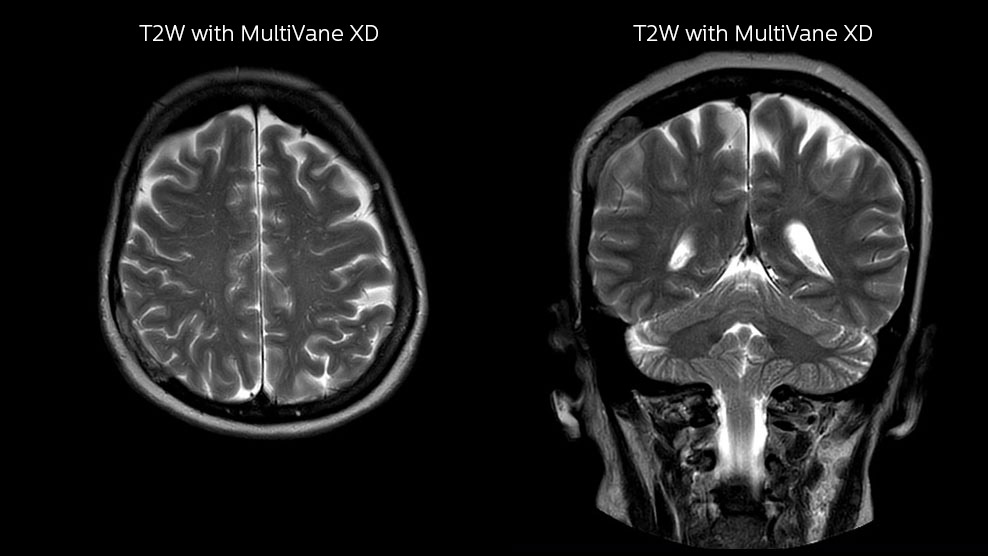

DMG recognizes MultiVane XD motion compensation is another Philips technique that contributes to image quality and scan efficiency. “We run MultiVane XD for motion-free imaging on almost all our T2-weighted brain scans, just to reduce any repeats we might get. We know our non-contrast brain scans are going to take 20 minutes almost every time,” Mr. Duffy says.

“Using MultiVane XD still allows us to turn on dS SENSE, which significantly cuts scan time compared to what we were doing before,” he adds. “We went from a 2.5 or 3-minute scan to a 1.5-minute scan with no loss in image quality. So, it not only reduces the motion, but also reduces scan time. That gives us a little bit of extra time to speak to our patients and explain the exam a little more.”